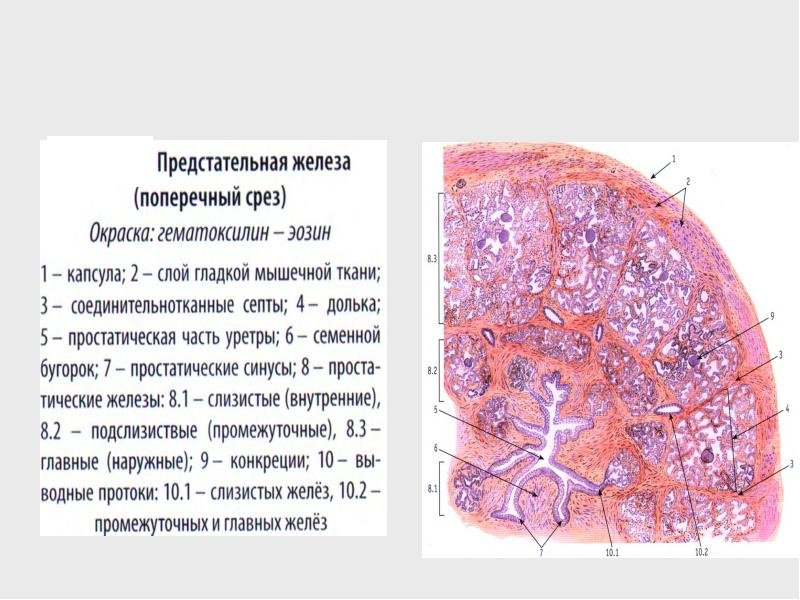

Простата детей